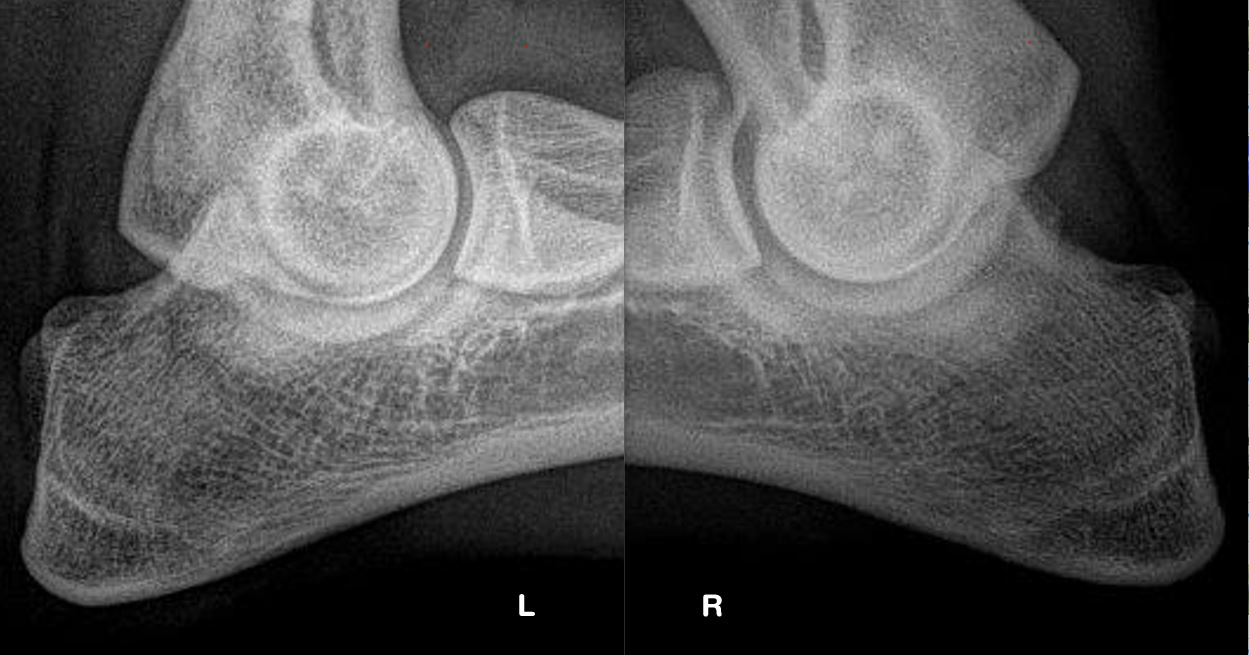

| ED : | LPC en artrose rechts (ED 0/3) (foto) | |